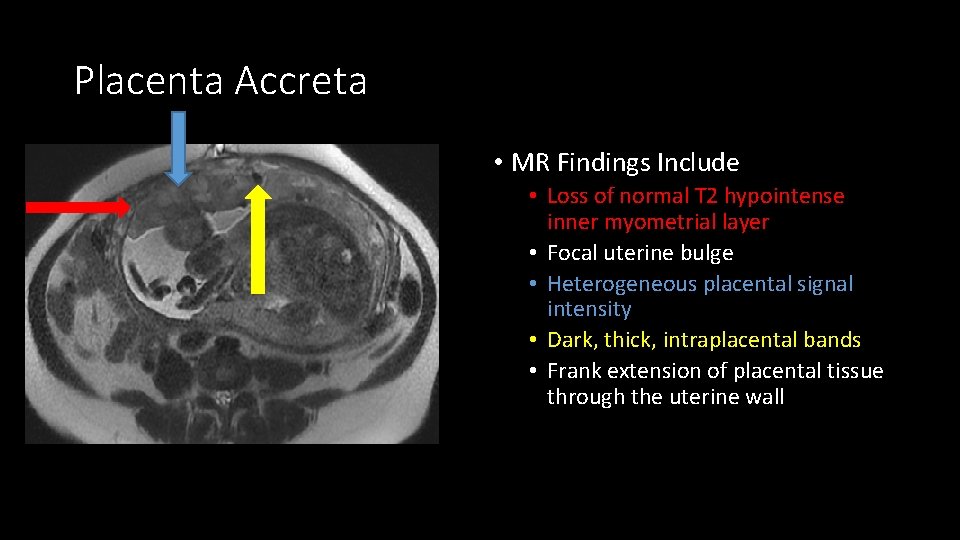

Placenta Accreta • MR Findings Include • Loss of normal T 2 hypointense inner myometrial layer • Focal uterine bulge • Heterogeneous placental signal intensity • Dark, thick, intraplacental bands • Frank extension of placental tissue through the uterine wall